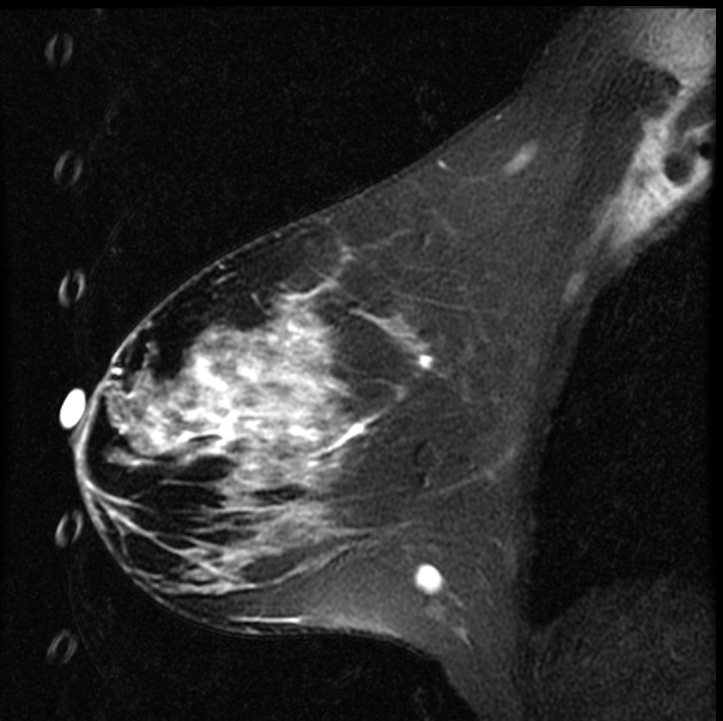

Enhancement - Subtraction Misregistration

Subtraction misregistration artifact on dynamic contrast-enhanced imaging. Ghost artifacts from cardiac and respiratory motion propagate in the phase-encode direction and produce false signal on the subtracted image, overlapping with true enhancing foci in the right breast. The ghost replicas alter local conspicuity and can mimic or obscure enhancement. Review of non-subtracted source images confirms which foci represent true gadolinium uptake.